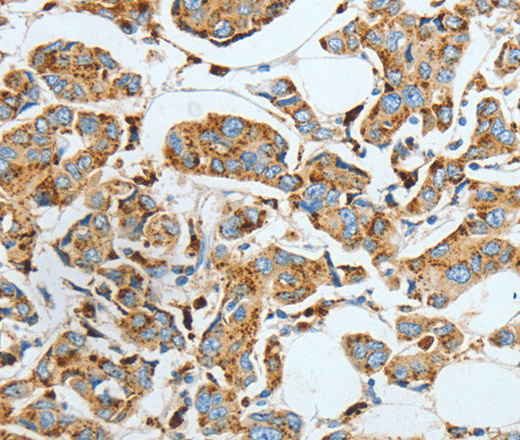

- Applications SupplierELISA WB IHC

- Scientific DescriptionThis gene encodes a heterodimeric protein consisting of a nonglycosylated alpha subunit and a glycosylated beta subunit that is cleaved to the mature enzyme posttranslationally. The encoded protein catalyzes the synthesis and degradation of ceramide into sphingosine and fatty acid. Mutations in this gene have been associated with a lysosomal storage disorder known as Farber disease. Multiple transcript variants encoding several distinct isoforms have been identified for this gene.